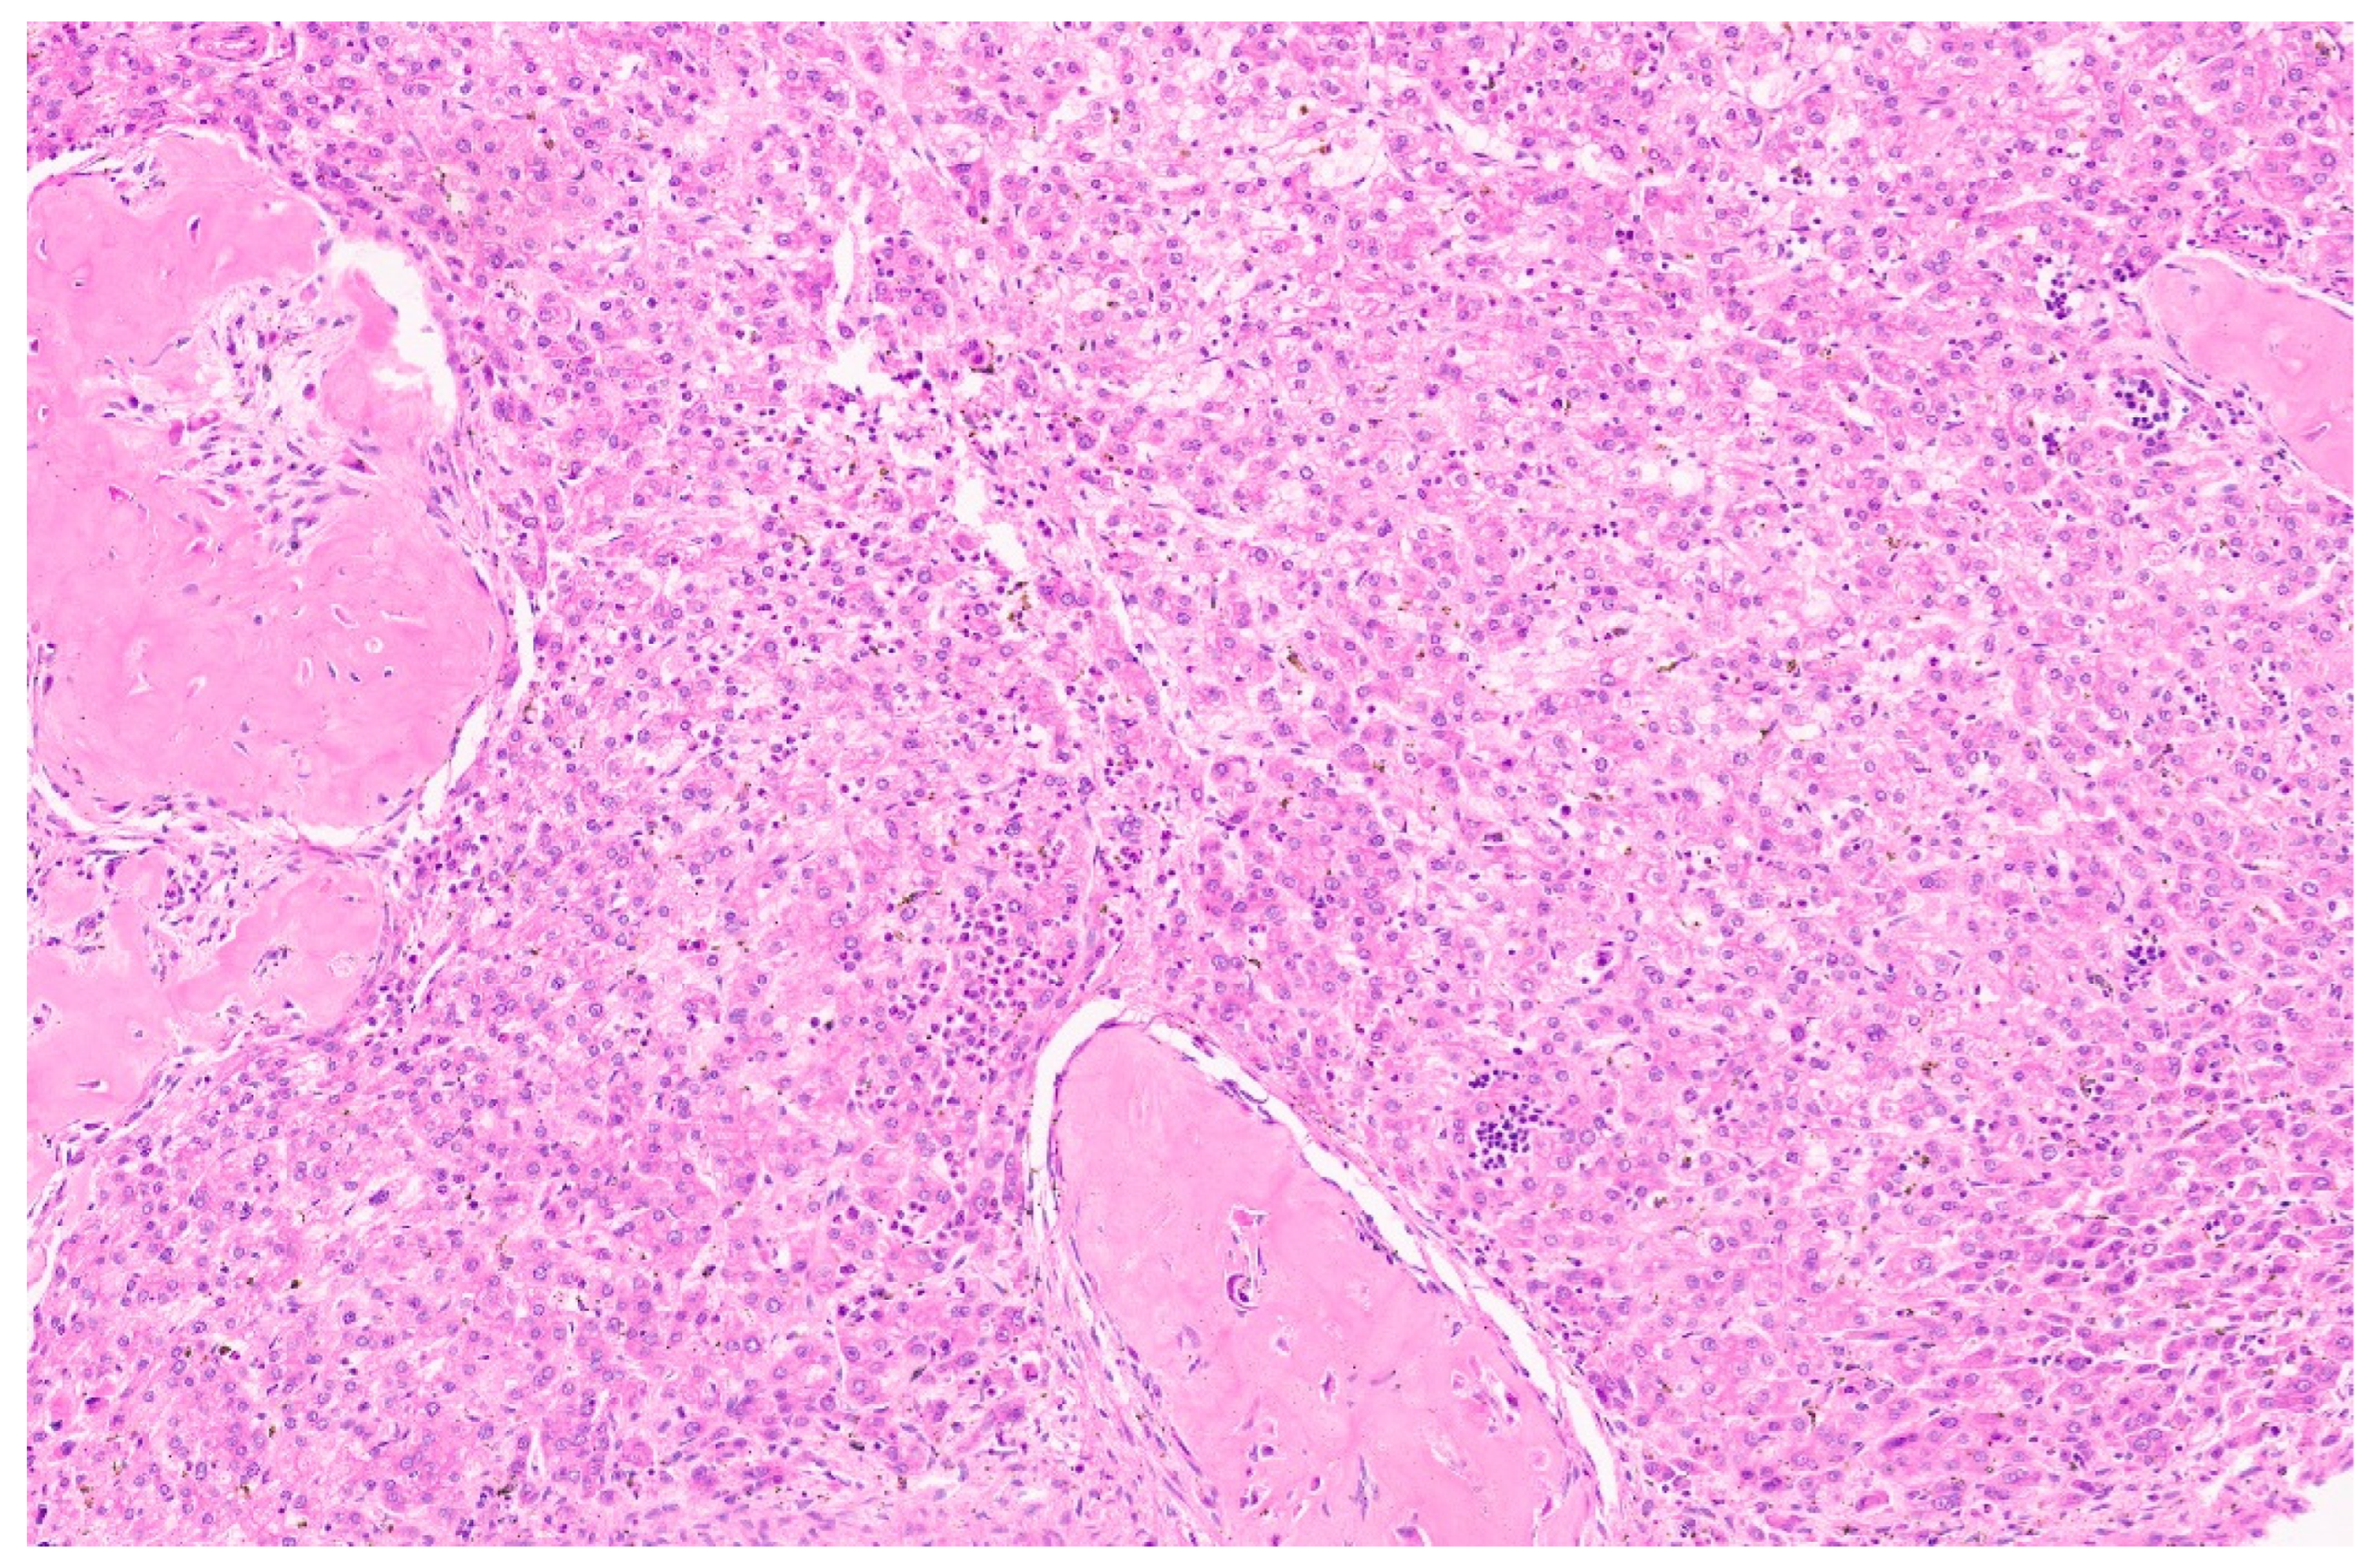

10.3. Pathology

15.3. Pathology